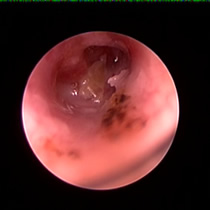

耳ダニ感染後の鼓膜喪失と中耳炎

長く耳ダニに気付かず治療が遅れた猫です。すでに鼓膜を失っており、中耳をきれいに洗浄すると赤い肉芽が確認できました。この肉芽を除去し点耳薬で治療すると改善。鼓膜が全く残っていないため鼓膜の再生は期待できませんが、痛みや痒みもなく元気に過ごしています。